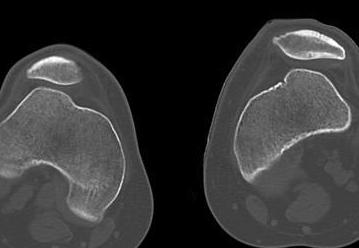

5. Trochlea dysplasia

- trochleoplasty

4. Lateral Trochlea Elevation

- still unstable after above operations

- small lateral incision

- beware fracturing lateral femoral condyle

- need to be able to take bone graft from iliac crest

1. Dejour Trochleoplasty

- lift up anterior aspect femoral condyles

- deepening of trochlea

- replacement of LFC

- risk of chondral fracture / AVN / non union / displacement

2. Elevate lateral edge of lateral femoral condyle

- insert osteotome

- gently elevate without fracturing chondral surface

- insert 2 - 3 mm of iliac crest bone graft

- no need for stabilisation